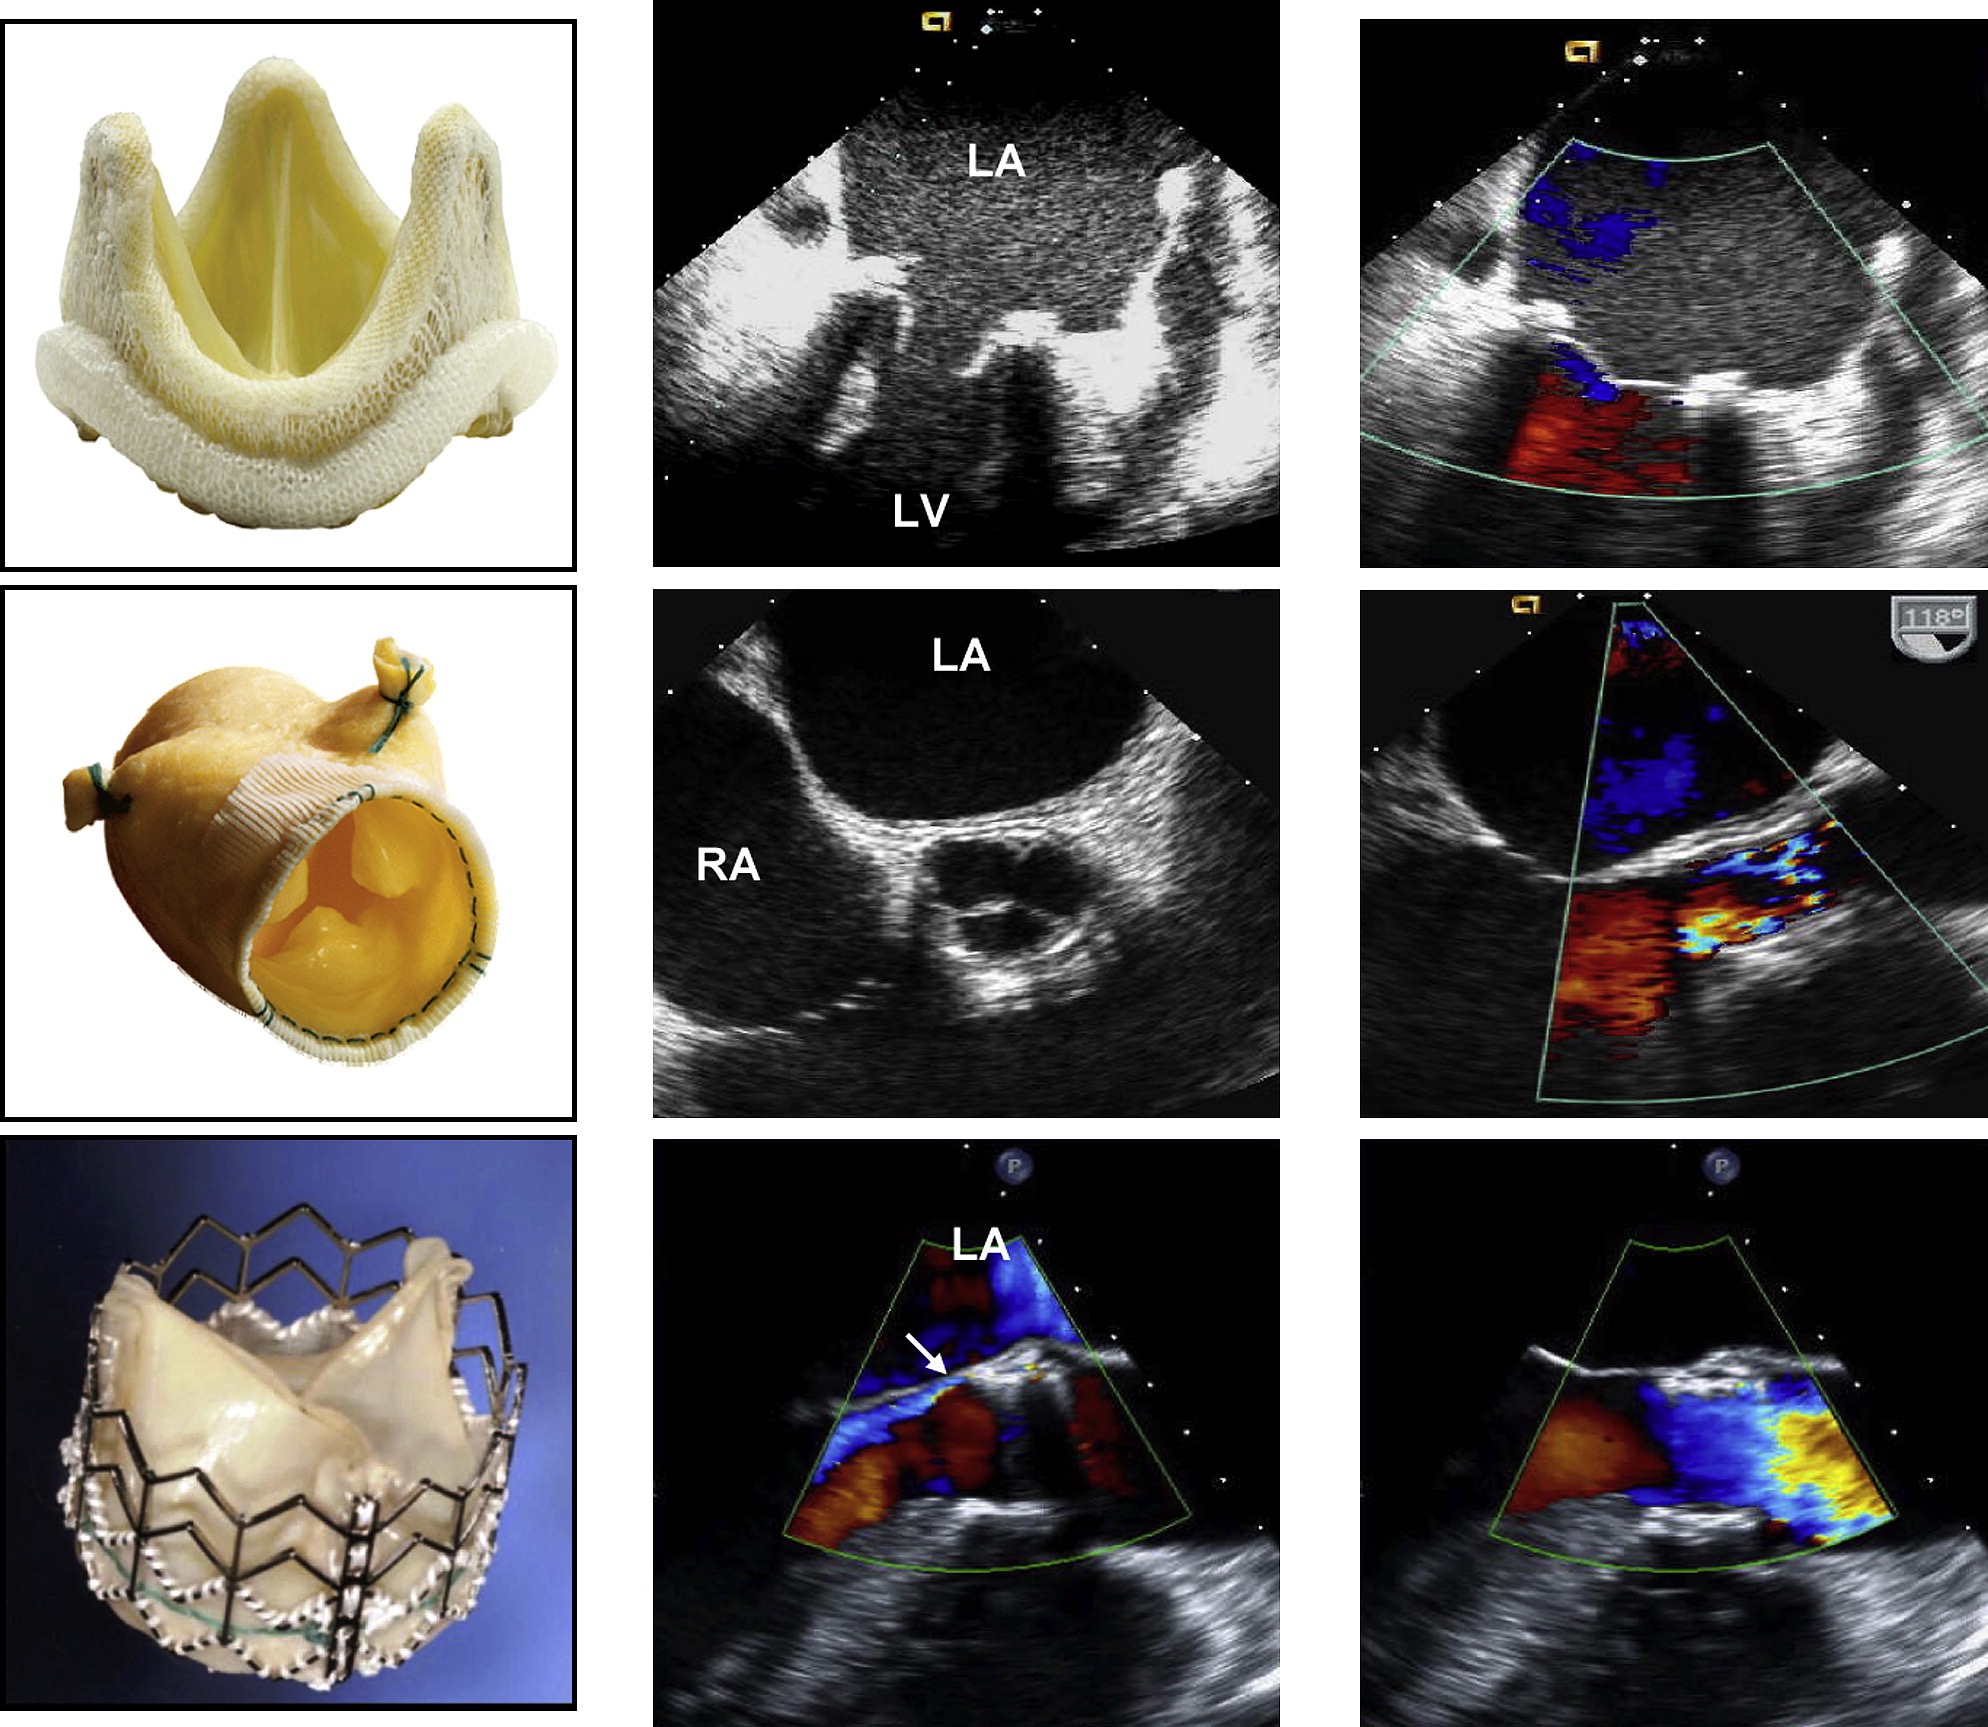

Examples of (A) bileaflet, (B) single-leaflet, and (C) caged-ball mechanical valves and their transesophageal echocardiographic characteristics taken in the mitral position in diastole (middle) and in systole (right). [2]

(A) 双叶瓣、(B) 单叶瓣和 (C) 笼形球状机械瓣及其在二尖瓣位置舒张期 (中) 和收缩期 (右) 的经食道超声心动图特征。

The arrows in diastole point to the occluder mechanism of the valve and in systole to the characteristic physiologic regurgitation observed with each valve.

舒张期的箭头指向瓣膜的封堵机制,而收缩期的箭头指向观察到的每个瓣膜特有的生理性反流。

# of Biologic Valves 生物瓣

Examples of (A) stented, (B) stentless, and (C) percutaneous biologic valves and their echocardiographic features in diastole (middle) and in systole (right) as seen by transesophageal echocardiography. [2]

经食道超声心动图显示 (A) 有支架、(B) 无支架和 (C) 经皮生物瓣膜及其舒张期 (中) 和收缩期 (右) 的超声心动图特征。

The stentless valve is inserted by the root inclusion technique.

无支架瓣膜是通过根部包裹技术植入的。

Mild perivalvular aortic regurgitation in the percutaneous valve is shown by the arrow.

箭头所示为经皮瓣膜轻度主动脉瓣周反流。